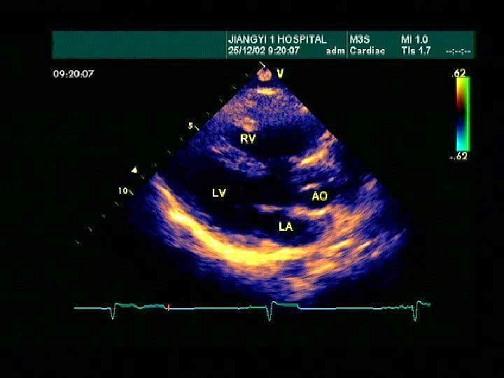

某患者左室长轴切面超声心动图如图所示,诊断为?(?)A.正常声像图B.扩张型心肌病C.房间隔缺损D.室间隔缺损E.三尖瓣返流

问题 某患者左室长轴切面超声心动图如图所示,诊断为?(?)

选项 A.正常声像图 B.扩张型心肌病 C.房间隔缺损 D.室间隔缺损 E.三尖瓣返流

答案 D